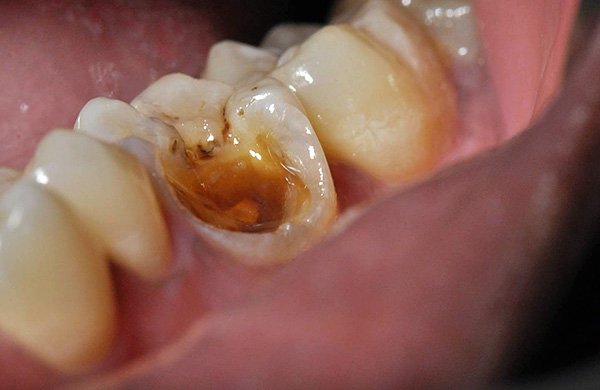

Le fotografie seguenti mostrano l'estrazione del dente, la cui parte della corona viene distrutta quasi al livello delle gengive:

Nel frattempo, se non lo tiri fino all'ultimo, allora sarà abbastanza semplice per il dentista rimuovere le radici del dente con una pinza, con le guance appositamente adattate per questo. Anche se le radici sono parzialmente serrate dalla gomma, le incisioni non vengono eseguite.Inoltre, le radici mancanti hanno una linea di accesso, cioè la gomma non può chiudere completamente il "putrido" anche nel corso degli anni, quindi il dentista-chirurgo deve solo aprirli un po 'con una spatola e rimuoverli con una pinza. Di solito ci vogliono circa 3-10 minuti.